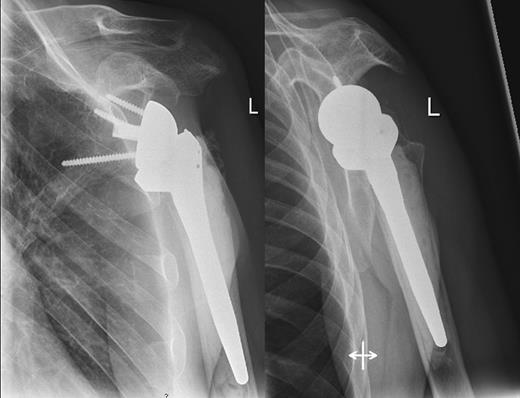

A 48-year-old patient was referred to a level I trauma center after the first incidence of an epileptic convulsion. The patient was alert and oriented with retrograde amnesia from the time of convulsion. Peripheral neurology was normal. The X-rays showed bilateral posterior shoulder dislocation with fractures of both humeral heads (Fig. 1). A CT of the head and both shoulders was performed to exclude intracerebral pathology and to achieve better demonstration of the shoulder fractures (Fig. 2). According to the AO fracture classification, he had a 11-C3.1 fracture on the left side and a 11-C3.3 fracture on the right side. The right side fracture was treated with a cementless hemiarthroplasty (OrTra®, Zimmer, Germany), while an open reduction and internal fixation (ORIF) with an angular stable plate (Philos®, Synthes, Germany) was performed on the left. Despite the high incidence for humeral head necrosis after ORIF in this fracture type, this option was chosen based on the young age of the patient. Postoperative X-rays and CT showed adequate positions of the implants (Fig. 3). The shoulders were immobilized in Gilchrist bandages followed by passive mobilization for the first 6 weeks by physiotherapy with a limitation for abduction and anteversion to 90°. There were no complications intraoperatively or in the first postoperative time. Patient was discharged after 8 days. Antiepileptic therapy was initiated with 5 mg clobazam and subsequent increasing doses over the following weeks. There were no more signs of epilepsy in the follow-up. A CT 4 months after operation showed dislocation of a fragment on the left side which was subsequently resected. At the 1-year postoperative review, the patient showed impingement of the left shoulder with abduction limited to 50° by both the plate and an osteophyte. Radiological assessment revealed signs of necrosis of the head. The plate was removed and the osteophyte resected. Eighteen months after injury, the left shoulder showed progressive avascular osetonecrosis of the head (Fig. 4) and after plate removal an inversed prosthetic replacement had to be performed (Fig. 5). At the last follow-up 3 years after injury, the patient was free of pain with a bilateral range of motion of 90° abduction and elevation.

Avascular head necrosis over the following one and a half years on the left side with ongoing necrosis after plate removal.

In our case, both operative procedures were performed. Owing to the young age of the patient (48 years), we tried to avoid acute prosthetic replacement of both sides. As the left side was less comminuted (AO 3.1 fracture type vs. AO 3.3 contralateral), we gave osteosynthesis a chance, being aware of the high incidence of avascular humeral head necrosis (AVN) in the literature with up to 50% as mentioned above. Unfortunately, AVN occurred over the time. The function of the right side after hemiprosthesis and on the left side after switching to an inversed prosthesis is free of pain with moderate range of motion.